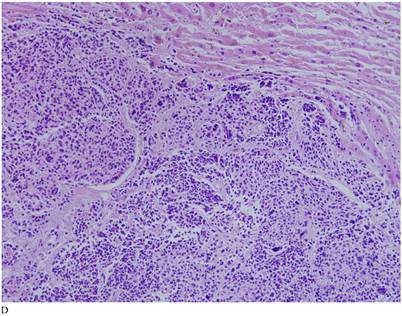

Case 1. A 79-year-old patient with a history of slowly increasing serum PSA levels for 2 years presented to the hospital with a 3-day history of fever. The patient's serum PSA level was 18.12ng/mL (normal <4ng/mL). Digital rectal examination (DRE) indicated grade III prostate enlargement. Magnetic resonance imaging (MRI) showed prostate cancer combined with right seminal vesicle invasion, pelvic lymph node, multi-bone, and liver metastases. An ultrasound-guided prostate biopsy was performed. Pathological examination suggested acinar adenocarcinoma. Gleason scores were 3+4=7. The patient was treated only with endocrine therapy because of his poor general condition. The patient died of respiratory failure caused by multiple metastases of the prostate cancer to both lungs 2 months later. Autopsy pathology revealed mixed SmCC of the prostate, combined with bilateral lung, liver, bilateral adrenal gland, pancreas, bone, and lymph node metastases. The prostate cancer was classified as SmCC with a mixture of acinar adenocarcinoma (Fig. 1A). All metastatic cancers were determined as pure SmCC without component of the acinar adenocarcinoma (Fig. 1B, 1C, 1D).

Case 1. Mixed SmCC. (A) Components of SmCC. (B) Components of acinar adenocarcinoma. Gleason scores were 3+3=6 combined with bilateral lung (C) and liver (D) metastases.

Two of our three cases of SmCC were mixed with acinar adenocarcinoma, and one was pure SmCC. Of the 26 cases in the literature reports, 21 cases were pure SmCC. Under the microscope SmCC tissues were flaky and in a nest-like distribution. Coagulative necrosis was also observed. The cells were small, like oat grains, with one end pointed and the other rounded. The cells contained only a small amount of cytoplasm, with the nuclei bared and darkly colored, and the nucleolus obscured; mitotic figures were frequently seen. For most cases, positive immunohistochemical staining for neurone-specific enolase (NSE), CD56, Syn, and CgA were detected, and immunohistochemical staining was positive for CK, producing a dot-like pattern. Local invasion, lymphatic vessel involvment, and distant metastases were found in 12 (46.2%), eight (30.8%), and nine cases (34.6%) respectively.

The confirmation of SmCC of the prostate relies mainly on pathological findings. Microscopically, SmCC cells are consistently round or short-spindle-shaped, arranged in a flaky or nest-like pattern. The cells only contain a small amount of cytoplasm, with the nuclei bared and darkly colored. The nucleolus is obscured and mitotic figures are frequently observed. Necrosis is also common. Immunohistochemical staining of SmCC cells for NSE, Syn, CgA, and CD56 is usually carried out for diagnosis [24]. Combined use of these four markers often results in a definitive diagnosis. Moreover, PSA, PAP, and P504S expression are rare in SmCC [8] and a CK-positive staining pattern in SmCC is characteristically dot-like. This can be used to differentiate SmCC from the poorly differentiated acinar adenocarcinoma.